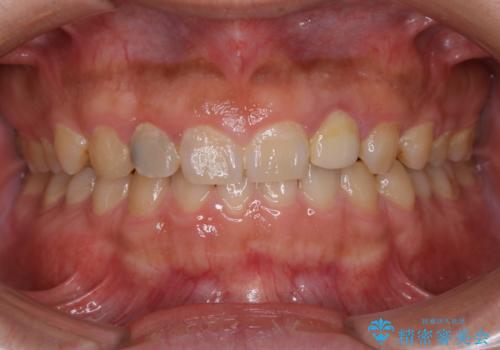

20年ぶりのクリーニングということもあり、歯の表面全てにプラークが付着していました。

プラークの細菌によりかなり歯ぐきが腫れていました。1度のクリーニングで汚れは落とせますが、このまま何もしないとまた同じようにプラークが付着し、それを繰り返すことになるだけでなく、歯周病や虫歯が進行してしまいます。そうならないためには、日々のケア、ホームケアがとても大事になっていきます。